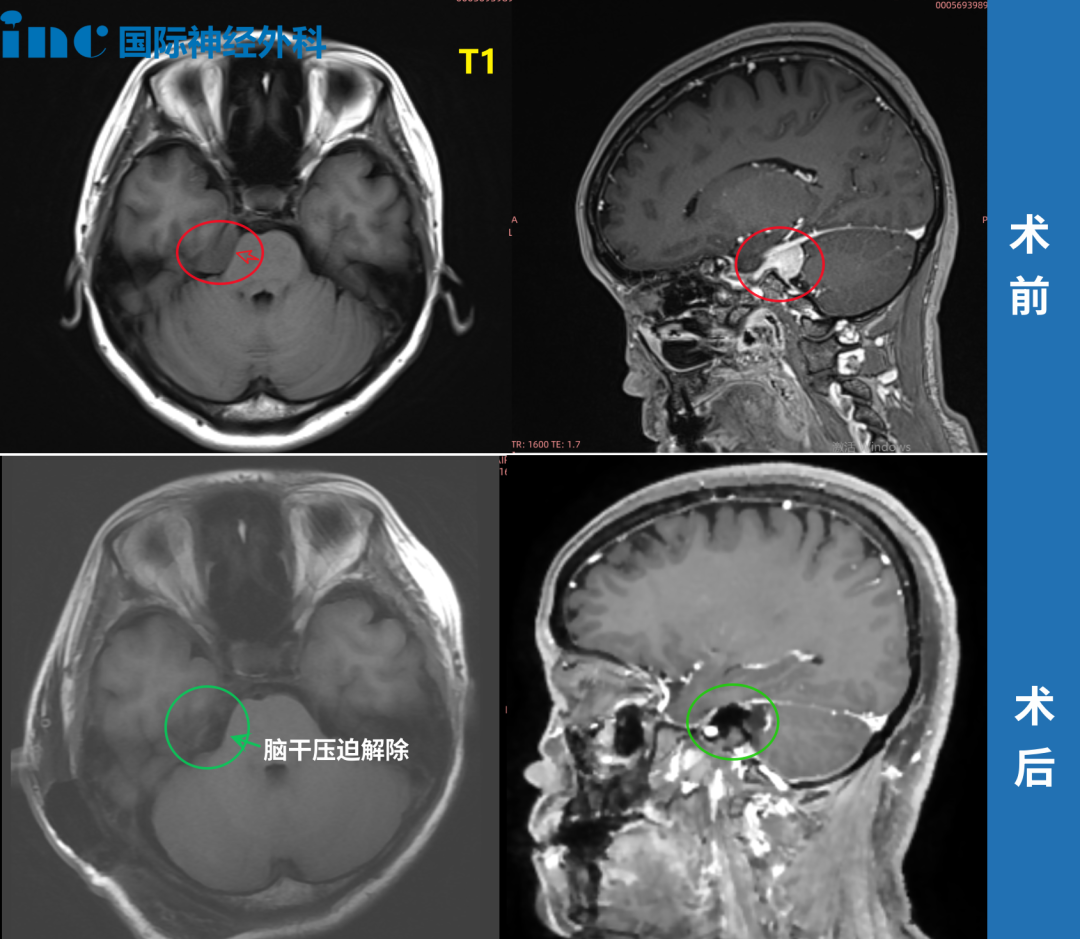

52岁钟女士也在体检中发现脑膜瘤。随后一年,她辗转多家医院,却屡被告知"手术风险过高"、"后遗症难料"、"难以全切"。焦虑使她夜不能寐,全家笼罩在阴霾中。直至伽马刀治疗效果不佳,她最终毅然选择手术,迎来生命转机。

41岁周女士同样在体检中发现桥小脑角(CPA)区脑膜瘤。肿瘤虽小,位置却极其棘手:与纤细的滑车神经、三叉神经紧密粘连,同时压迫桥脑和中脑——这是生命中枢。她未等到剧烈头痛或面瘫偏瘫出现,正是这份体检报告,让她在神经功能尚完好时抓住治疗"黄金窗口期",最终由巴教授主刀完成高难度手术,及早解除风险。